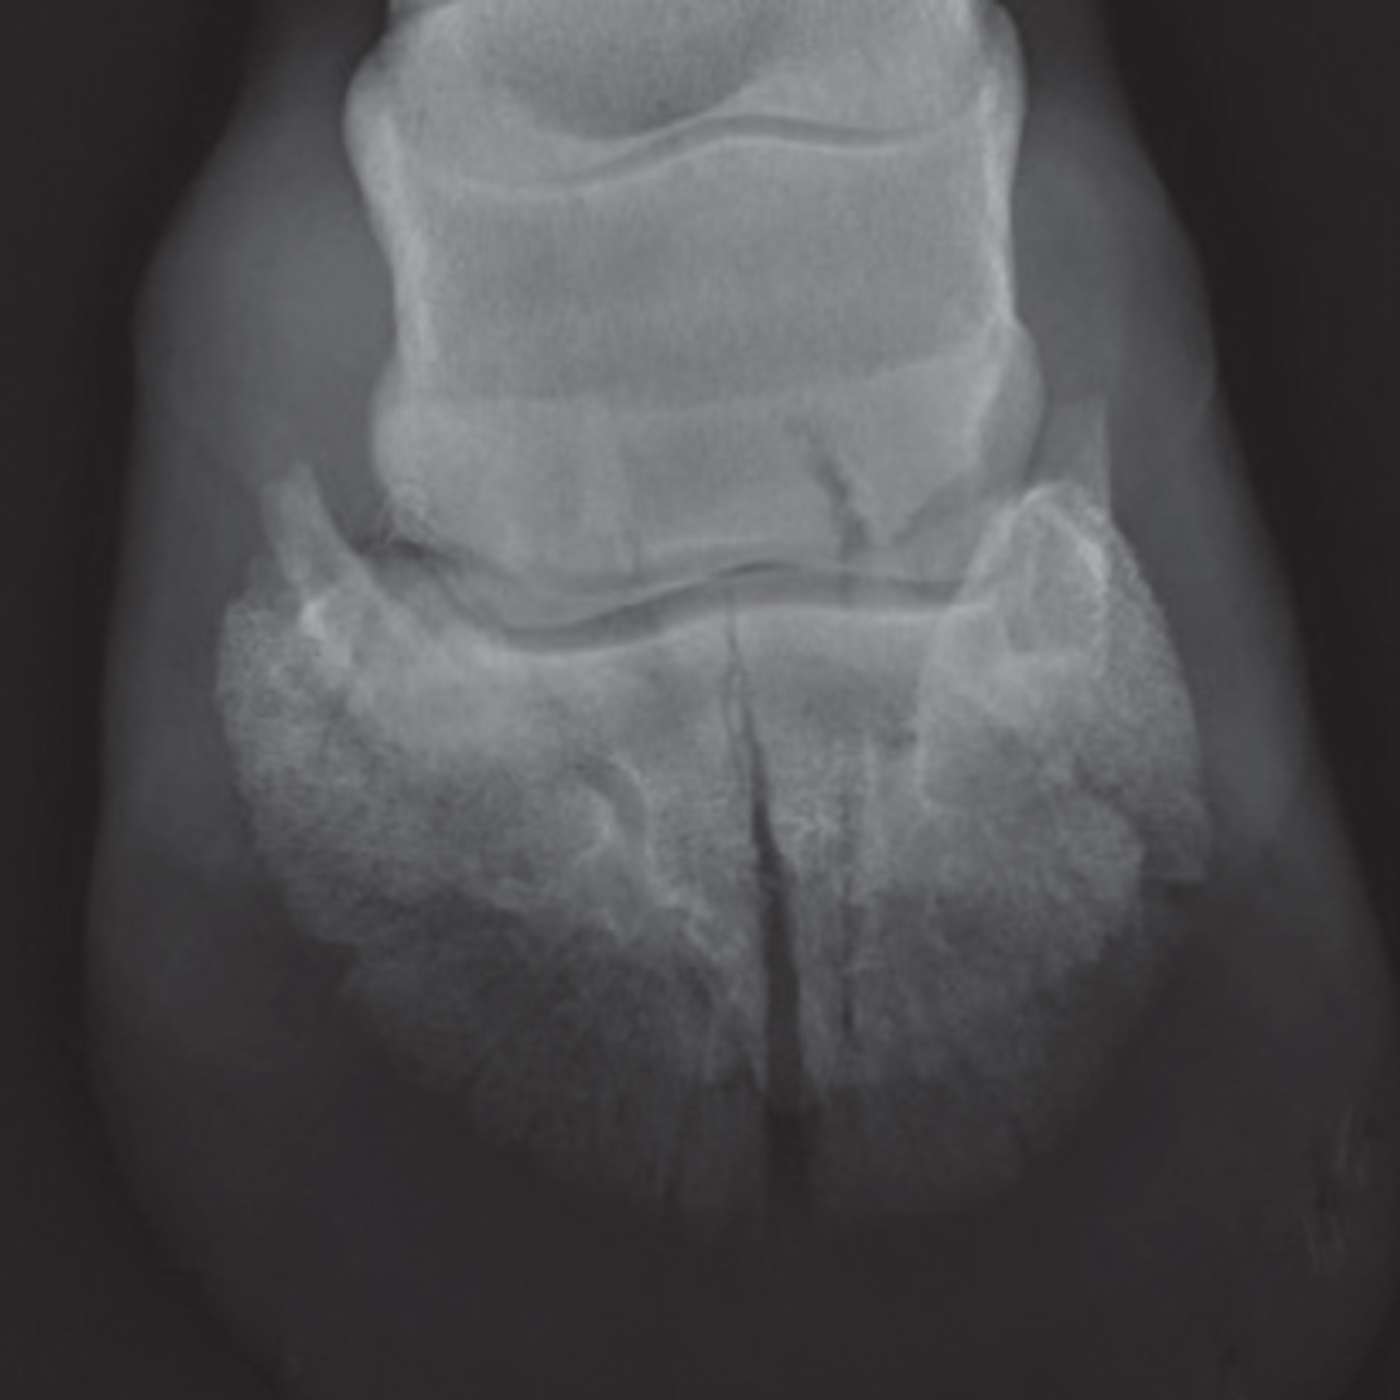

In this episode, we explore coffin joint arthritis, a common yet complex cause of lameness in horses. Discover how this degenerative joint condition affects performance, and how diagnostic tools like nerve blocks, radiographs, and advanced imaging guide precise farriery and veterinary treatment. We discuss trimming and shoeing strategies to relieve joint stress, supportive therapies such as joint injections and biologics, and practical owner management tips including exercise, envi...